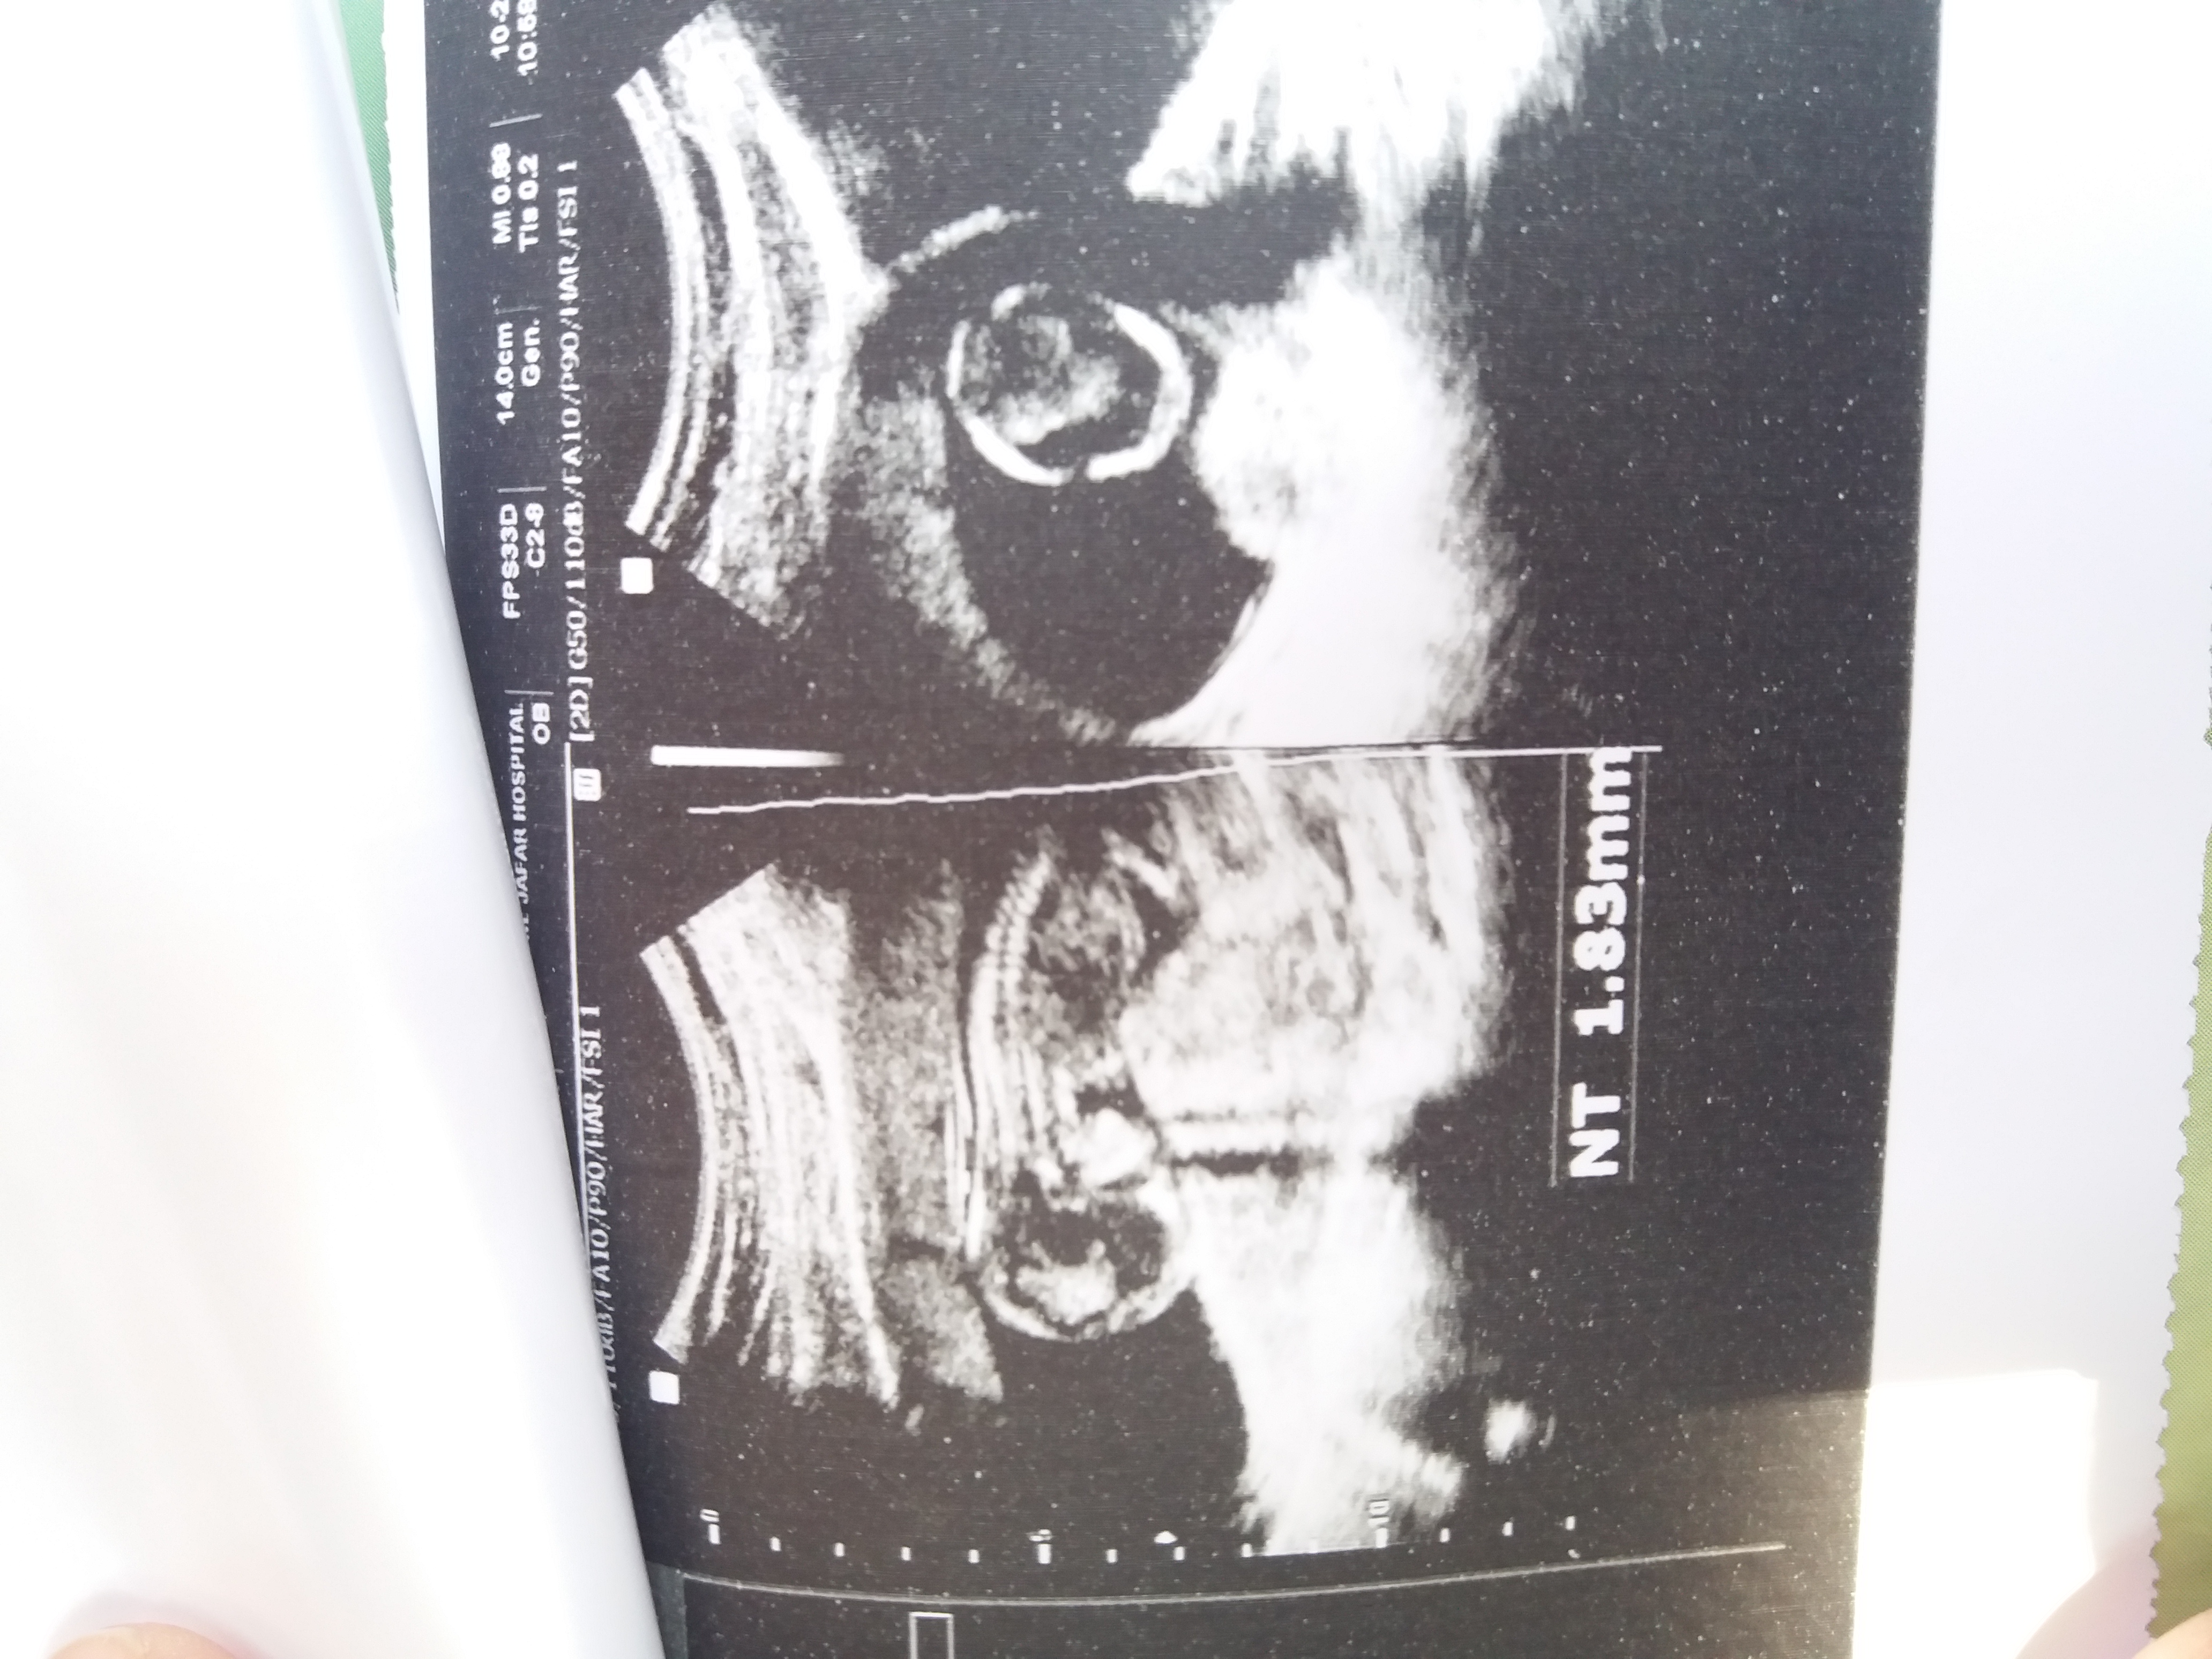

فرزووونه76سابقم عضویت: 1396/11/24 تعداد پست: 9568 گوشی رو بچرخونین دخملمه تو سیزده هفته و چهارروزگیش ک دراز کشیده بهم بگید براتون حمد بخونم